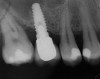

A full-thickness mucoperiosteal flap was raised, and alternating osteotomes were used to prepare the implant site. After achieving a length of 7 mm (Figure 7A and Figure 7B), heterologous bone graft was implanted and the osteotome sequence was repeated. The implant showed primary stability.

Figure 7a  Alternating osteotomes with variable conicity used to perform the alveolar remodeling in the area of tooth No. 15.

Figure 7a

Figure 7b  Alternating osteotomes with variable conicity used to perform the alveolar remodeling in the area of tooth No. 15.

Figure 7b